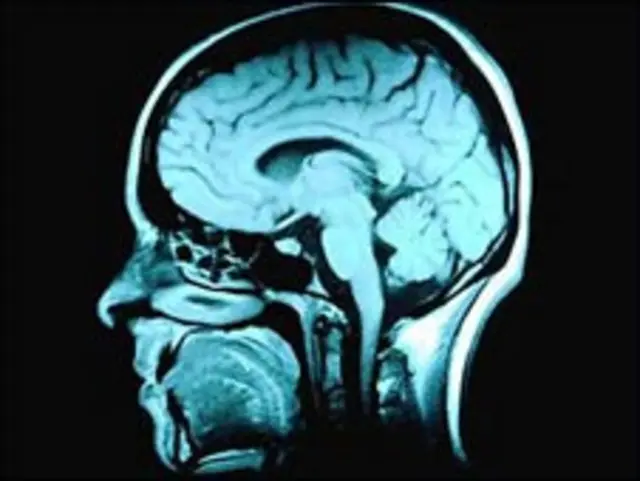

英国南汉普顿大学信号控制和处理研究室的科学家们最近在大脑与电脑接口技术(或称脑机接口,BCI)技术上有了新成果,给人科幻成真的感觉。

据介绍,所谓脑机接口技术就是把大脑发出指令转化为电脑可识别和执行的指令。

据称,人脑在发出指令时,眼球会有微不可测的光感变化,而可以探测到这些变化的光感仪器,就可以把这些变化翻译成电脑可读0或1组成的语言。